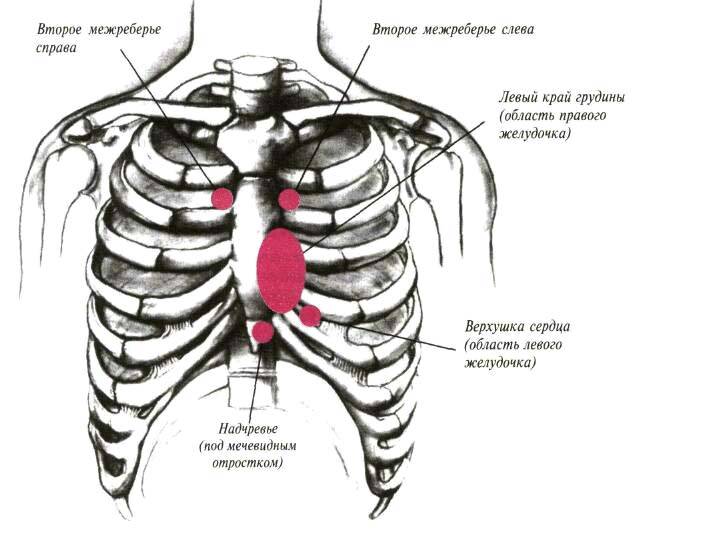

Причины и лечение боли в грудной клетке при кашле